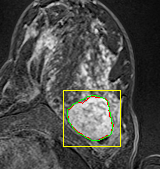

In MR images, tumor regions are normally brighter and have more uniform intensity than the neighbouring healthy tissue. Based on this fact, we determined the internal and external markers by sorting out the pixel values in ROIs in descending order and chose pixels with maximum intensity values as markers. After selecting the markers the normal watershed transformation is applied on the ROIs image which is shown in Fig 1 Finally, a binary mask is generated based on watershed output regions. However, we identified the optimal number of markers based on segmentation accuracy evaluated using Dice and Jaccard.

We tested the algorithm by varying the number of markers between and . Fig 2 describes the segmentation results obtained using different numbers of markers. This plot indicates that markers were found to be optimal using this segmentation approach, yielding satisfactory results.

where refers to the ROIs segmented by our algorithm and is tumor area as determined by manual segmentation. Table 1 summarizes the segmentation accuracy achieved using the proposed method for all 106 cases. The average dice coefficient was found to be 0.780.17 and average Jaccard index was 0.670.21. Fig 3 demonstrate four sample segmentation outputs which are overlaid on manual segmentations provided by two radiologists. It can be seen, that the proposed method could accurately segment the lesions with some marginal errors for medium to large tumors. However, for cases comprising disjoint lesions, the method failed to segment all small lesions and in some cases incorrectly labeled healthy tissue as lesions. This is because in some cases there is a high degree of overlap in the intensity distributions of healthy breast tissue and lesions, and the ROI drawn by the radiologist is very large in the case of disjoint lesions, in order to cover the entire area over which multiple lesions are distributed.